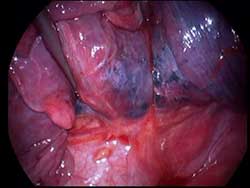

Prior VATS lobectomy is a relative contraindication to ipsilateral repeat VATS lobectomy due to possible technical difficulties arising from adhesions and scarring, especially at the hilum. This video describes a VATS middle lobectomy in a 63 years old ex-smoker who in 2005 had a VATS right lower lobectomy for stage I squamous cell carcinoma. In 2008 he developed pulmonary tuberculosis of the right upper lobe that was successfully treated with anti-tuberculous medications. Then, in 2009 he underwent a successful right VATS middle lobectomy for a metachronous squamous cell carcinoma that was clinically stage I on CT and PET scan.

The original VATS incisions were reused. Chest wall and hilar adhesions were taken down meticulously. Lobectomy was accomplished by stapling the middle lobe vein first, followed by completing the fissures between upper and middle lobes. This helped in identifying the middle lobe pulmonary artery branches in the fissures. After ligating and doubly clipping the middle lobe pulmonary artery branches, they were divided. The right middle lobe bronchus was dissected and then divided with an endostapler. The bronchial stump was sealed with tissue glue. Operative time was 3 hours and 15 minutes. The hospital stay was 4 days and patient is well with no recurrence 12 months after surgery. The pathologic stage was T1N0M0, stage 1a.